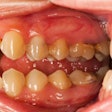

Inflammation key to understanding periodontal disease

February 14, 2012